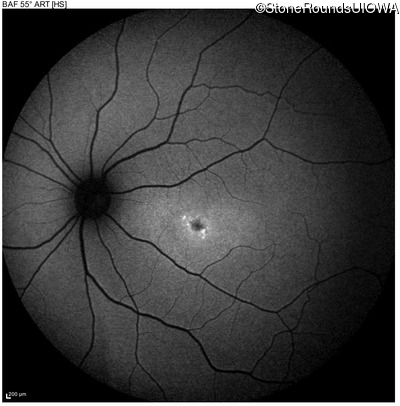

Age at visit: 17 years

OD OS

This 17 year old female first noted problems with her visual acuity around age 13 when she had trouble seeing the projector from the back of the classroom.